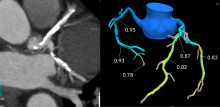

One of the big trends in cardiac computed tomography (CT) imaging has been the introduction of noninvasive fractional flow reserve CT (FFR-CT), which can be used instead of a catheter-based FFR in the cath lab. FFR-CT is being claimed by both cardiology and radiology. The critically important question, however, transcends turf issues. Will patients suspected of having coronary artery disease benefit from its use?